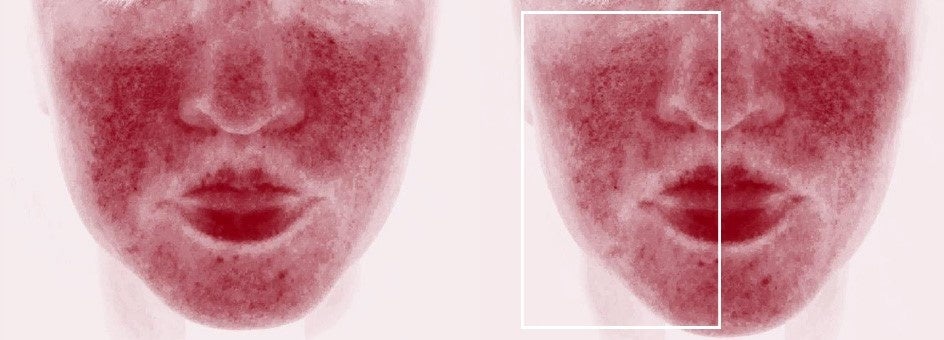

症例1

症例2

上下ともに:機器治療後、半顔だけにAIR(アイル)を20分適用し、前後にヘモグロビン強調画像を撮り検証した。上の症例写真は、右側(向かって左/囲み内)の赤みがより減少、下の写真は、左側の赤み(向かって右/囲み内)がより減少しており、どちらも赤みがより減少したほうがAIR(アイル)を適用した側だった(画像提供:奥謙太郎院長)。